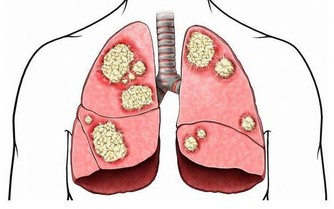

缺鐵性貧血不僅僅是貧血這樣簡單,它能夠導致機體免疫力的下降,降低人們對疾病的抵抗能力。而且,缺血即缺氧,骨骼肌中的呼吸酶、線粒體氧化酶等含量都會下降,致使患者出現乏力、氣喘、活動力下降等表現。

缺鐵貧的患者需要尤為小心心血管事件,貧血是個全身性的疾病,機體處於一個缺氧的狀態,所以全身的各個臟器都會受到影響,只不過,相較於其他的器官,心臟、大腦這些用氧量更多的器官,受到的波及會更大,既往有冠心病、腦梗等患者需要格外小心。